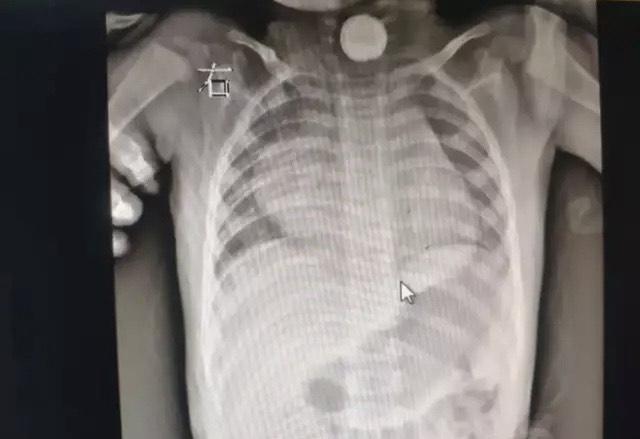

她提醒,若孩子在进食过程中突发呛咳、剧烈咳嗽,应高度怀疑发生异物吸入。需要注意的是,如果异物较小或已进入支气管内,可能一段时间内无明显症状,往往容易被忽视。

“孩子久咳不好时,也要排除是否有异物吸入。”郑亦男介绍,小异物吸入进入气管后,容易引起气道炎症,孩子会表现出久治不愈的慢性咳嗽、肺不张等症状。如果发现孩子有慢咳,咳痰带血、呼吸困难等症状鼓励家长带孩子来医院正规就诊,查明原因。临床上曾有异物在气管里几个月都没发现的病例,异物被增生的肉芽组织包裹,非常难以取出。